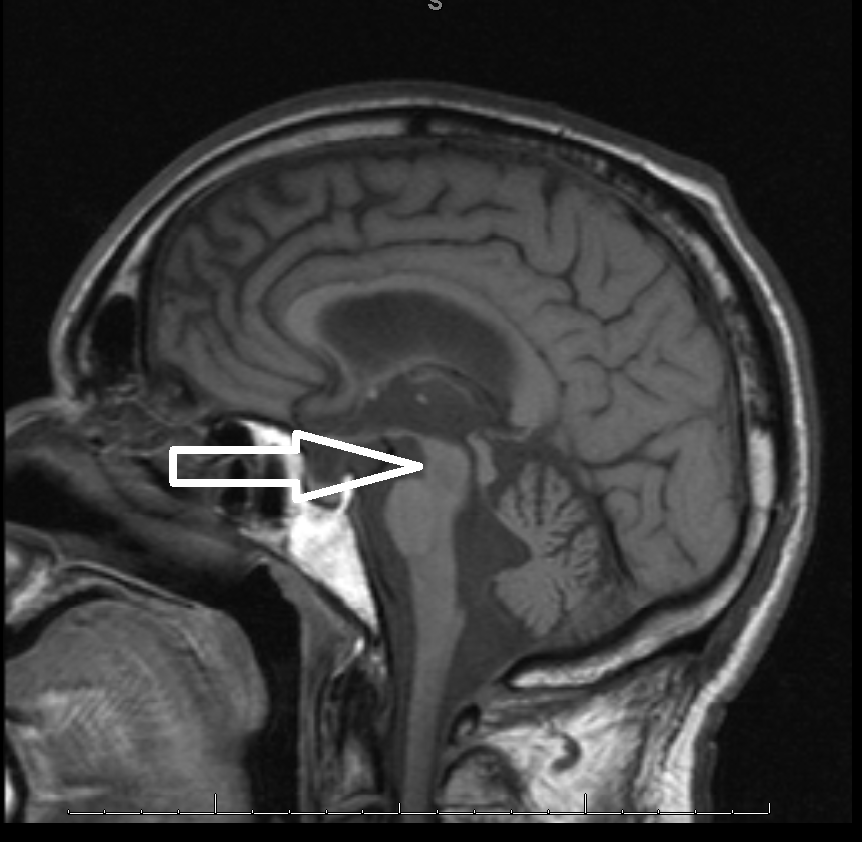

Middle age male patient admitted for evaluation of syncope. He has a history of coronary artery disease, severe pulmonary HTN, COPD, anemia of chronic disease, Osteoarthritis, left vocal cord paralysis, orthostatic hypotension, unsteady gaits and previous syncopal episode. CT head imaging remarkable for cerebellar atrophy. MRI done showed moderate cerebellar atrophy, midbrain atrophy with hummingbird sign and hot cross bun sign in the pons representing neurodegenerative disease multisystem atrophy and progressive supranuclear palsy.

Magnetic Resonance Imaging (MRI) is the modality of choice – atrophy of putamen, middle cerebellar peduncle, or pons on MRI is supportive for possible MSA. MRI radiographic features include hot cross bun sign, atrophy of cerebellum and midbrain, putaminal rim  sign.